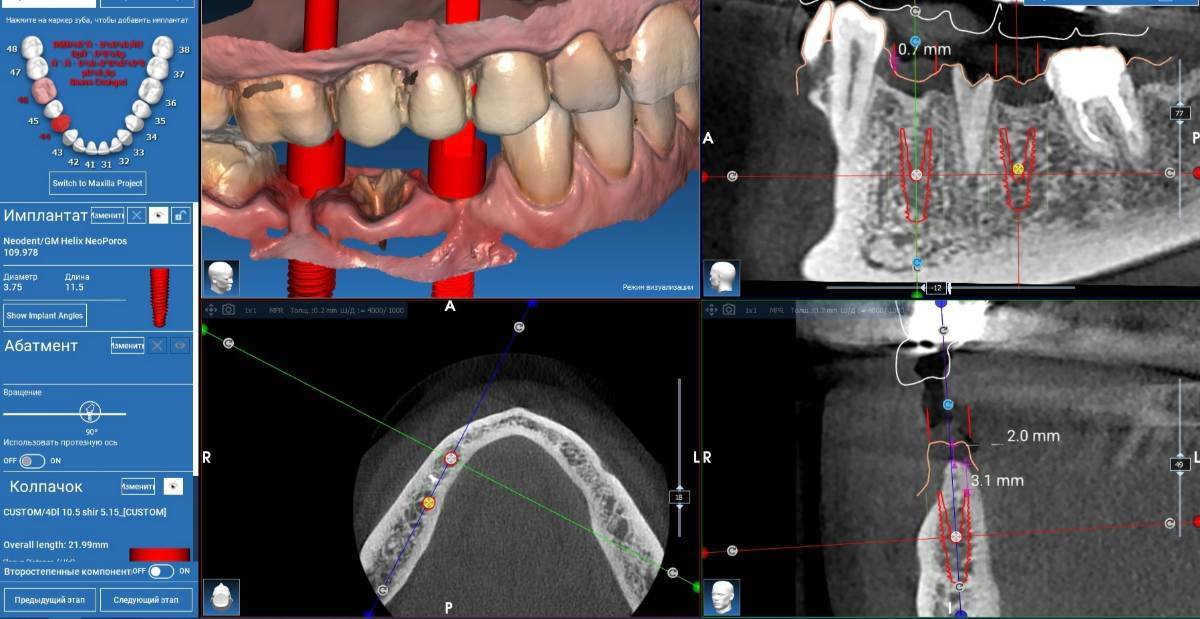

Fin Опубликовано 5 июня, 2025 Поделиться Опубликовано 5 июня, 2025 Здравствуйте коллеги. Хотел бы представить вашему вниманию первую часть кейса по восстановлению 4 сегмента. Перелом зуба 4.5 под мостовидным протезом 4.7-4.4. 4.7 решено оставить до последующего повторного протезирования При планировании имплантации вестибулярное оголение имплантата на 1.5-2мм в области 3. 4. Дефицит керотинизированной слизистой оболочки. Более глубокое положение имплантата приведет к чрезмерному количеству сзизистой оболочки в 7-8 мм. Решено не пытаться использовать ССТ с целью перекрытия оголенного имплантата а попробовать технику морковки профессора Кюри. 1 этап операции. Удаление зуба 4.5, подготовка костного ложа под имплантаты при помощи трепанов и запор костных морковок, установка имплантатов неодент 3.75х10 в позицию 4.4, 4.3х10 в позицию 4.6, ушивание. 2 этап. Создание прикрепленной слизистой. Расщепление лоскута, удаление пиноа, пересадка СДТ с фиксаций его этими же пинами. 3 этап. Открытие имплантатов с установкой ФДМ и снятие швов через 2 недели. Решил не добавлять ССТ. На данный момент ожидаем полное восстановление тканей и приступаем к этапу протезирования. Так как параллельность имплантов достаточна планирую протезировать с уровня имплантатов. 3 2 1 Ссылка на комментарий